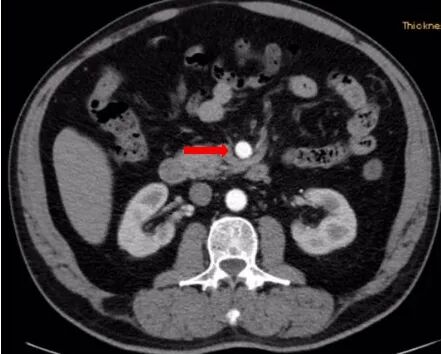

术前查腹腔动脉CTA示:肠系膜上动脉夹层伴动脉瘤。

患者肠系膜上动脉夹层动脉瘤,真腔明显缩小,假腔增大,有胃肠道缺血表现,有手术指征,未见手术禁忌。

术前造影图像